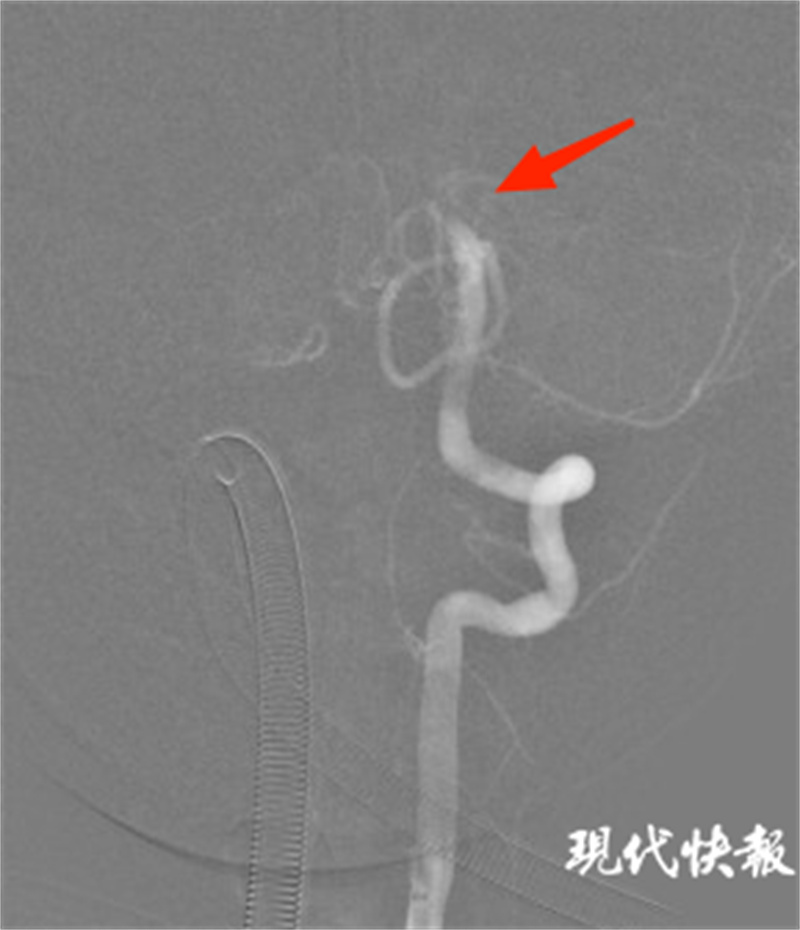

△术中脑血管造影可见双侧椎动脉V4段汇合处栓塞

术中造影确认为双侧椎动脉V4段汇合处栓塞。随后引入神经微导管、微导丝及取栓支架,行机械取栓,取出较大血栓块。造影证实血管恢复血流通畅,取栓成功,手术顺利结束。